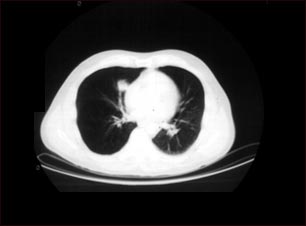

Nódulo pulmonar, pulmón inferior derecho - Tomografía computarizada

Tomografía computarizada que muestra una masa en la parte inferior derecha del tórax, cerca del corazón (lado izquierdo de la fotografía).